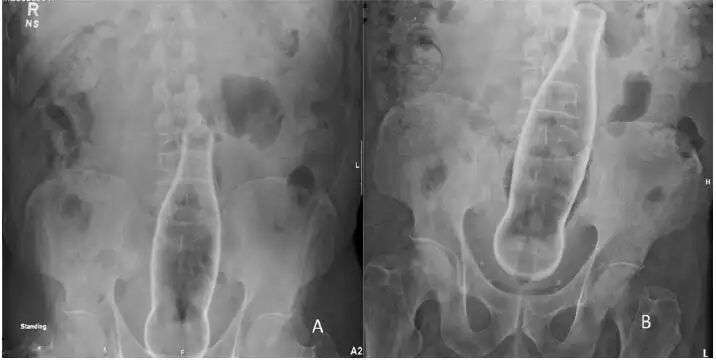

拆弹专家很快辨认出炮弹来自一战时期,已经有100多年历史,长约20cm,直径约4cm,过去的德意志帝国制造。

根据其口径和生产日期,专家判断这枚炮弹很可能是用于高射炮或反坦克炮的。

而它从未被发射过,目前处于完好无损状态,也就是说,仍然具有杀伤力,危险性基本和100多年前保持着一样水平…